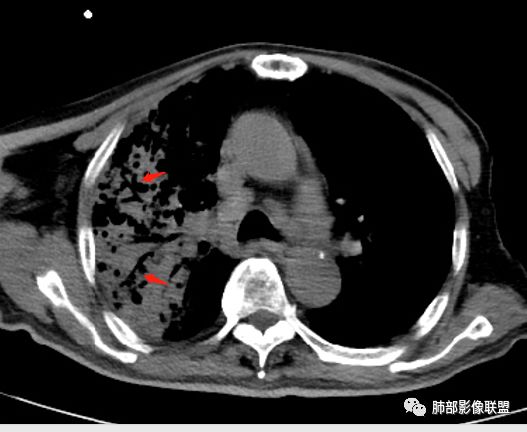

老年男性,咳嗽气喘10天,双肺明显肺气肿,右上肺叶实变,内见大量空洞及囊腔样改变(部分为支气管扩张),实变区周围表现为网格样改变,有明显的小叶间隔增厚,边界似清非清,支气管走行僵硬,有枯树枝样改变,双下肺胸膜下小叶间隔增厚明显,边缘相对模糊,综合考虑如下:1、粘液腺癌可能大(枯树枝样改变,边界似清非清,小叶间隔增厚符合)。2、结核,右上肺似像干酷样改变,内有空洞及支扩样改变支持,但下肺及左肺无相关支气管播散的小叶中心结节及树芽,不支持,临床病症不支持,只有咳嗽,喘气,无咳痰及结核中毒症状。当然结核是妖,需要结合痰检及结核相关指标进一步明确。3、肺克,虽有10年糖尿病史,但肺部只有右肺改变明显,无胸膜下脓肿表现,无脓毒栓表现,临床症状也不支持。4、其他感染?双下肺胸膜下病灶边缘模糊,不完全除外,需要结合临床炎性指标分析。

支气管、内部的小囊腔,部分无壁小空洞,病灶部分边界偏清,支持结核

1、结核干酪空洞常很干净,很彻底,而粘液腺癌空洞内有液性成份,不干净。

2、支气管:干酪样肺炎内的支气管破坏的,扩张的,粘液腺癌小支气管多狭窄的堵塞的,大支气管较完好,枯枝征。

6、结核灶周围磨玻璃少见,粘液腺癌磨玻璃影清楚。结核灶常有收缩,钙化,树丫等等。很重要,粘液腺癌分布弥漫,远处飘散的边界清楚的磨玻璃结节影有重要诊断意义。

7、形态,结核收缩,粘液腺癌局部膨胀,叶间裂有时候是膨胀下坠的。